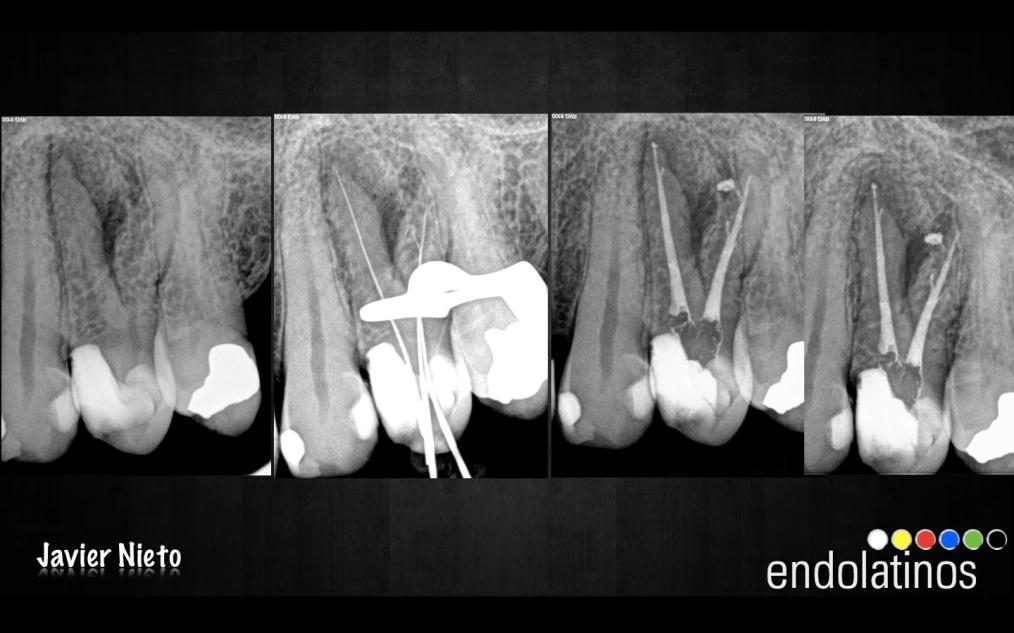

Caso 3:

Este último caso, se trata de una necrosis de una pieza 2.4 con gran lesión apical. Lo publiqué por el motivo que a veces, localizamos unos conductos laterales o accesorios y lo complicado que nos resulta el saber si lo hemos obturado completamente. Siempre nos queda esa duda, son los límites que nos encontramos en un tratamiento por vía ortógrada, no podemos pretender manejar todas las situaciones de manera perfecta. Aunque este caso, en el que buscamos el éxito con la regeneración y curación de la lesión, nuestra finalidad es la perfección, obviamente imposible.